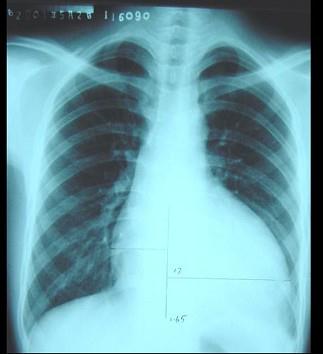

问题 男性,17岁,检查发现心脏杂音四年,活动时心慌、气促三年。血压130/20mmHg,主动脉瓣区舒张期杂音,心脏正位片如图所示,该患者最可能是何种心脏病 ( )

选项 A、主动脉瓣关闭不全 B、三尖瓣关闭不全 C、主动脉瓣狭窄 D、二尖瓣关闭不全 E、二尖瓣狭窄

答案 A